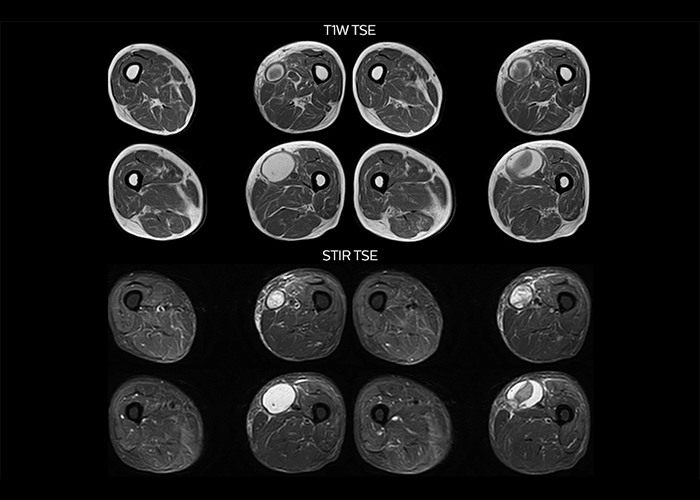

“On average, we scan about 80 patients per day, but on some days we scan well over 100 patients. The scanner is in use 7 days per week, operated 20 hours per day on week days and 8 hours per day in the weekend,” Mr. Tuna says. “To avoid coil changes we plan examinations of similar anatomies back to back, such as head and spine. Multiva helps us here a lot because coils don’t need to be changed frequently. Moreover, thanks to parallel imaging technology and 16-channel HeadSpineTorso and 8-channel MSK coils we are able to achieve excellent image quality. In this way Multiva helped us to increase both image quality and productivity.” “Neurological cases, such as brain and spine imaging, represent the largest share in our MR scanning, followed by musculoskeletal cases. In general, we use simple and basic imaging protocols. But occasionally, we use advanced techniques for problematic cases if necessary.